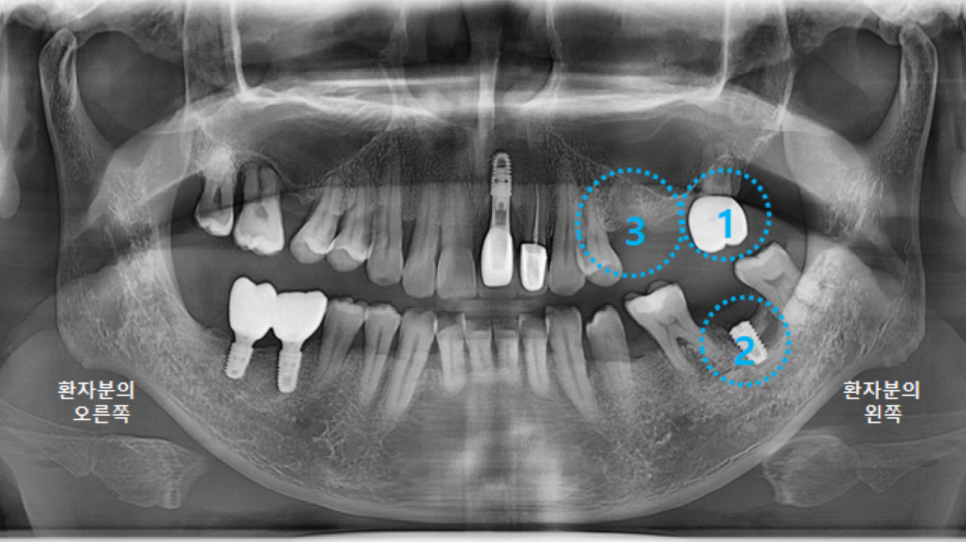

그리고 다시 파노라마 엑스레이를 촬영했습니다.

최상의 컨디션은 아니지만,

어느정도 치유가 되었기에 3차원 CT 촬영 후, 왼쪽아래 큰어금니 임플란트 수술을 진행하도록 합니다.

앞뒤 인접치의 관계도 고려하고,

3차원 CT로 봤을 때, 뼈가 더 많이 차있는 안정적인 위치를 선택합니다.

그런데 왼쪽 위에 브릿지가 없어진 사실을 눈치 채셨나요?

상태가 좋지 않은 작은어금니는 발치하기로 하고

중간에 하나 없는 큰어금니까지 임플란트를 2개 심기로 결정했습니다.

그리고 제일 마지막에 있는 큰 어금니는 발치할 정도까지는 아니라서

일단 살려서 사용해보기로 결정했습니다.